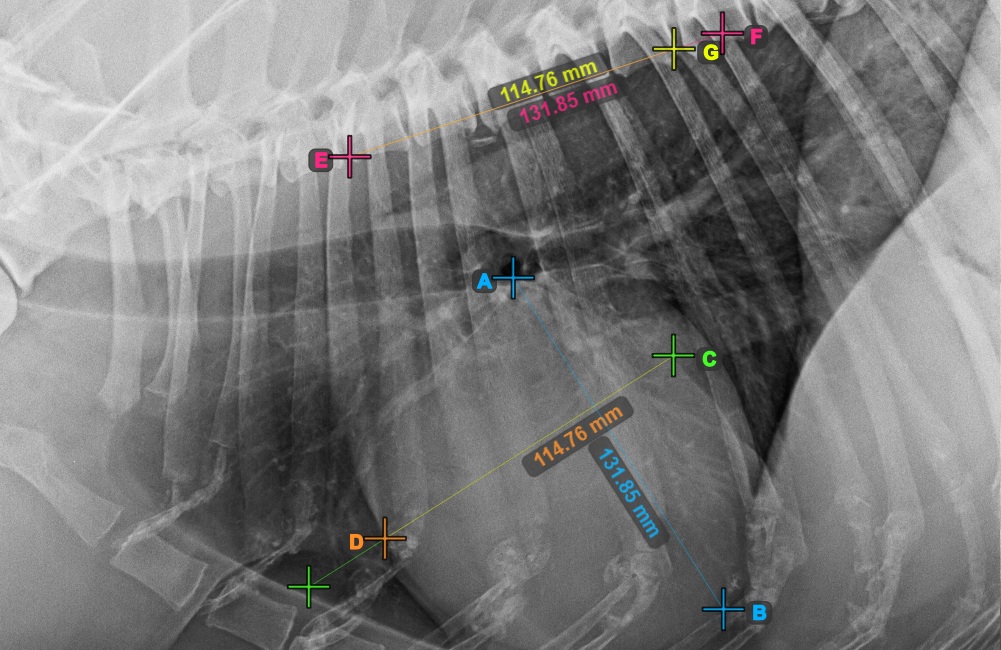

Identify the beginning of the T4 vertebra (the fourth vertebral body of the spine), counting from the initial point of the spine. Mark the beginning of the T4 vertebrae to continue the measurement. The software will draw lines from the marked point along the spine. The length of the lines depends on the measured long and short axes of the heart.

The image below represents the typical placement of the point at the beginning of the fourth vertebral body of the spine.

Before proceeding with the required VHS calculations, make sure that the lines are placed precisely along the vertebrae.

Count the number of vertebrae along the line representing the short axis on the spine. Specify the required vertebrae count in the Vertebrae Count input field in the advanced measurement mode toolbar.

Press Calculate VHS Score to perform the required calculations for the VHS measurement. The VHS score will be shown in the advanced measurement mode toolbar. Additionally, the VHS score will be labeled on the image, as part of the measurement.